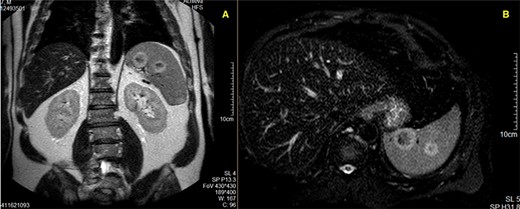

MR Imaging showing two nodular formations with the same ring-hypersignal pattern; A—T1-weighted acquisition; B—T2-weighted acquisition.

A magnetic resonance imaging (MRI) study (Fig. 2) was then ordered, and it described a spleen with regular margins and slightly enlarged, with its longitudinal axis measuring 14.3 cm. In the splenic parenchyma, multiple nodular lesions were detected, at least nine, with dimensions measuring up to 29 mm. These nodular formations were solid, heterogeneous, and showed a progressive and predominantly peripheral contrast-enhancement. They presented hyposignal in T1 and peripheral hypersignal in T2-weighted acquisitions, without any relevant restriction to diffusion. This absence of restriction to diffusion suggests benign nodularity; however, these features are not specific. Malignant splenic disorders could not be excluded.

Despite the apparent lack of specific diagnostic criteria, imaging studies can be of great importance. CT and MRI distinguish benign vascular lesions from each other and from malignant lesions. However, when compared with SANT lesions, metastasis behaves in a similar manner. Both may be solitary, multiple, or diffuse and appear as hyperintense masses on T2-weighted images and hypo- to isointense masses on T1-weighted images, usually with a peripheral ring-like pattern [9, 8]. Some authors postulate that imaging features such as arterial or portal venous phase peripheral enhancing radiating lines, progressive enhancement on CT scan imaging, also associating hypointense T2-weighted signal intensity in a gadolinium-enhanced MRI study should suggest SANT. A “spoke-wheel” pattern on MRI may be an important imaging clue for making the correct diagnosis [10].